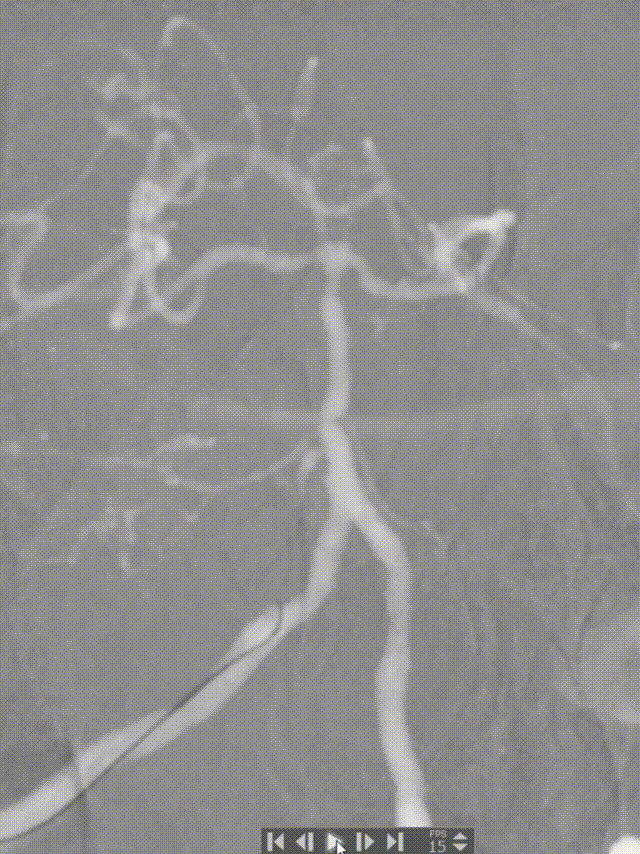

6F 90cm 长鞘+5F 115cm 通桥银蛇®颅内支持导管建立通路。

0.014in*200cm 微导丝超选,球扩支架 2.5*8mm到位。

充盈球囊支架释放。

术后造影:基底动脉狭窄消失,双侧AICA通畅。